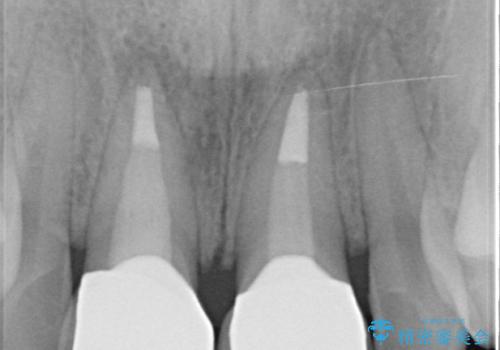

- 歯ぐきの黒っぽさ、暗い色調の前歯の改善を求めて来院されました。

金属を用いたコア・クラウンが装着されており、全ての金属を除去したのちのメタルフリー治療を計画します。

ファイバーコア・セラミッククラウンは金属を用いない審美的な治療法です。